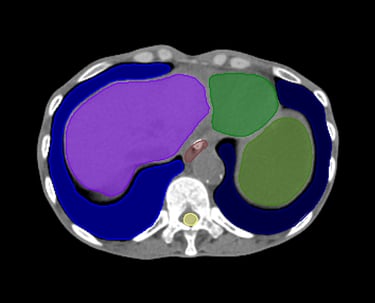

O SegmentaR foca na segmentação automática das três regiões fundamentais para o planejamento de radioterapia: cabeça e pescoço, tórax e pelve. Essas são as regiões essenciais que todo profissional precisa para uma segmentação precisa e eficiente.

Tórax

Coração

Duodeno

Esôfago

Estômago

Fígado

Laringe

Medula Espinhal

Pulmão Direito

Pulmão Esquerdo

Rim Direito

Rim Esquerdo

Glândula Tireoide

Traqueia

Mama Direita

Mama Esquerda